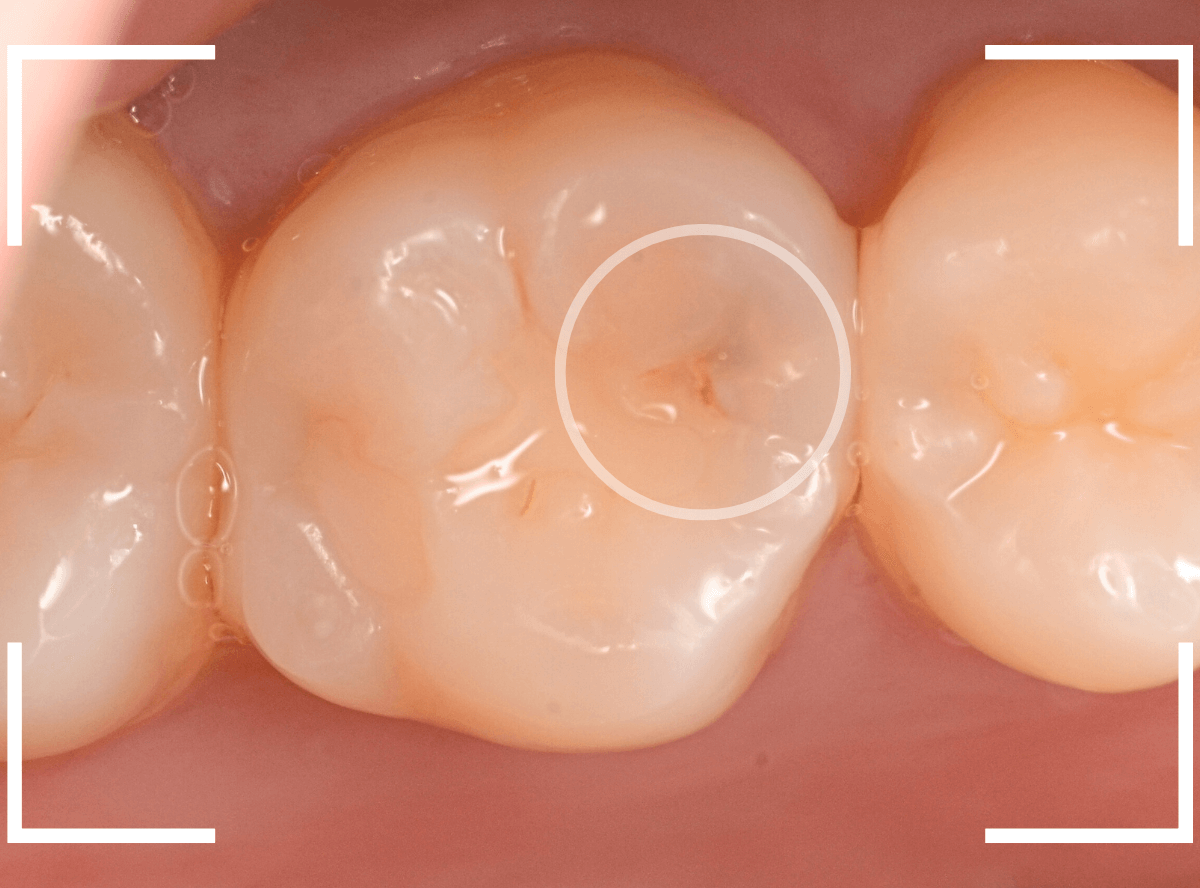

Case.10 レントゲン写真でしか虫歯がわからなかったケース

検診希望で来院された患者さんの例です。

レントゲン写真で、後ろの歯との間に虫歯が見つかりました。

大きな虫歯になっていると考えられます。

上から見ただけでは私でもどこが虫歯かわかりません。

今回はレントゲン写真で明らかに判別できましたが、虫歯の診断はドクター間でも意見が別れる時があるほど、奥深く難しいです。

自己判断はくれぐれも禁物です。

治療を始めて、虫歯の部分をう蝕検知液で染め出したところです。

真っ赤ですね。

慎重に虫歯を除去しますが、まだ虫歯が残っています。

虫歯を除去しました。

なんとか神経ぎりぎりのところで踏みとどまりまし

た(^^;)

いつものように、症状がでないかしばらく経過観察です。

お薬をつめてしばらく経過観察した後、特に症状などもありませんでしたので、つめもの(インレー)で歯の形を再現する事になります。

今回は良い素材の物で治療したいとのご希望でしたので、セラミック素材(E-MAXインレー)で治療をする事になりました。

歯の形をトリミングして、型どりをします。

E-MAXインレー、Set後の状態です。

自然な見た目で治療出来たかと思います。

セラミック・インレーは、歯への密着性が高いため、金属のインレーよりも虫歯の再発が抑えられる(だからといって、メンテナンスが必要ないわけではありません)というメリットもあります。

| 治療回数 | 3回 |

| 治療期間 | 約3週間 |

| 費用 | E-MAX・インレー (50,000円) +保険治療費用(虫歯除去など) |

(2024年5月)